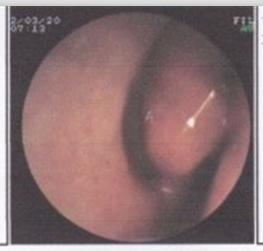

【鼻甲肥大的预防保健】现在的社会环境正在不断的恶化,导致鼻甲肥大的发病率也在不断的上升,身边的亲友们也都多多少少患有鼻甲肥大的困扰,贵阳耳鼻喉医院专家指出鼻甲肥大的危害是很大的,不容忽视,在生活中也会给患者造成很多的影响,所以我们不能忽视鼻甲肥大的存在。以下就是我院专家就鼻甲肥大为大家介绍的内容。